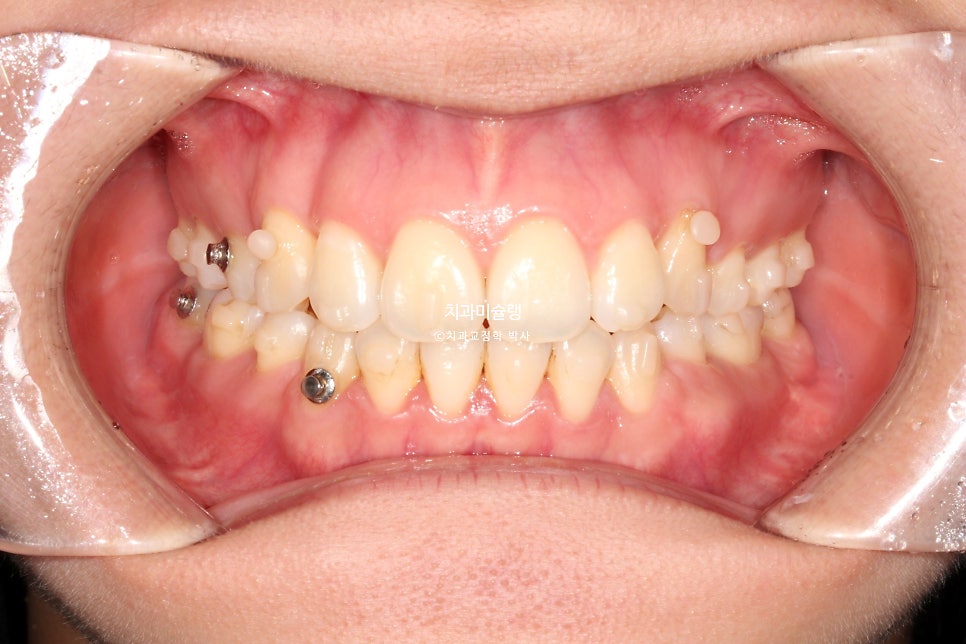

그렇게 추가장치를 끼며 중간에 무사히 출산도 하시고, 23개 장치를 다 낀후 내원시 모습입니다.

중심선 교합은 좋고 발치공간도 타이트 하게 마무리 되었습니다.

2026년 2월 치료 완료

18개 추가장치를 모두 낀후 2026년 2월, 드디어 치료를 마무리 했습니다.

어금니 교합은 좋으며 1급 교합관계를 보입니다.